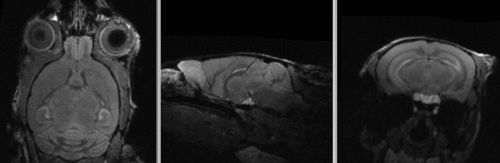

shown are, from left to right, panels of axial, sagittal and coronal views.

original brain in non-RAS orientation original, not RAS

original brain in proper RAS orientation original,after reorientation into RAS